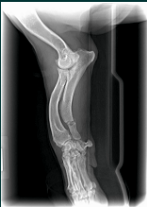

Hey Bob,Sorry, Ive been in and out of town.  I've attached some radiographs of a 12 year-old dog with an ulnar fracture we've been using it on.  It looks like we have significant callous formation in 16 days!  I have another dog that I did a patellar luxation surgery that we are using it on as well.  I'll try to get you some films of it.  So far I haven't had any major issues.  It would be nice if the device itself could be smaller for some of these smaller dogs.  The fracture dog has a bandage/splint on, so it is pretty easy to encorporate the coils into the bandage.  The other dog has no bandage, so I've been using elasitcon to hold it over the affected area.  After a 4-5 days it causes some irritation and we have the device off a couple of days before replacing it.  I'm not sure there is any other way to hold it there(over the knee) without putting a bandage over the leg which would limit our range of motion and cause muscle atrophy.Thanks,

Ian Voeizel, DVM